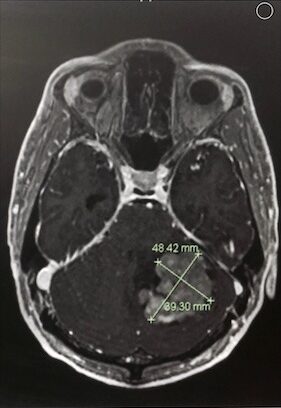

After that injury, I felt like I lost my self-worth, and I lost my purpose and my identity, and I fell into addiction. After my addiction progressed for a while, I was then diagnosed with this medulloblastoma. It was slightly smaller than a tennis ball in my cerebellum, the back part of my brain here. It was surreal with that diagnosis. I didn’t know how to face it or what to think. I went through multiple brain surgeries, chemotherapy, and radiation. After that, I was just at rock bottom. I just didn’t know how to live at that point, and what a difference ten years makes.

We got into a little argument about it because she thought I was just using drugs again. But when I got dropped off there, when you go in complaining about your head and the symptoms I was talking about, they immediately got me right into the doctor and to the MRI. That’s when they diagnosed me. That picture is part of the cover of my book, too.

I had to have multiple brain surgeries because, for the treatment to work, they had to remove the tumor completely. For me to have a chance at recovery, they had to remove the tumor completely, and then chemotherapy and radiation — that was the treatment. They had to remove it, and then that was the treatment. In the first surgery, they only got 80% of it, so they had to do an MRI after, and that wasn’t fun. Then they had to go back the next day and take the other 20% out.